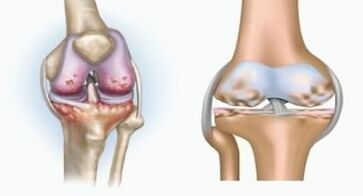

Ambas patologías afectan las articulaciones, pero difieren en la naturaleza de los cambios.

Con artritis

La artritis es una inflamación del tejido conectivo, una membrana sinovial que contiene muchos vasos y proporciona flujo linfático. El proceso inflamatorio conduce a una violación de la nutrición de los tejidos articulares, como resultado de la cual la producción de lubricación articular - líquido sinovial es limitada.

Con artrosis

La artrosis es un proceso degenerativo-distófico asociado con la destrucción del tejido del cartílago de la articulación. El cartílago se destruye gradualmente, seca, la distancia entre los huesos de la articulación disminuye, que es la causa del dolor. En formas severas, la destrucción afecta a los huesos. Se vuelven más porosos, pierden su densidad, se vuelven frágiles.

Por ejemplo, ¿cuál es la diferencia entre la artritis y la artrosis de la articulación de la rodilla? Con la artritis, se produce la capa sinovial de los tejidos articulares. Esto causa un aumento de la temperatura en la articulación.

La articulación aumenta, se desarrolla un síndrome de dolor persistente, que se intensifica durante el movimiento. Con la artrosis, el dolor ocurre solo después de la actividad física, puede escuchar un crujido o clics característico en la articulación, gradualmente la articulación se deforma y pierde movilidad.

La diferencia entre la artritis y la artrosis de los dedos y las manos de las manos es que la primera enfermedad se cura y la segunda no. Con la artritis, se toca la carcasa sinovial y la cápsula de la articulación.

La derrota del cartílago y el tejido óseo ocurre solo en las últimas etapas en un estado descuidado. Con la artrosis, el tejido del cartílago se ve afectado primero, y luego el hueso, la inflamación de la membrana sinovial es de origen secundario, es decir, se desarrolla contra sus antecedentes.